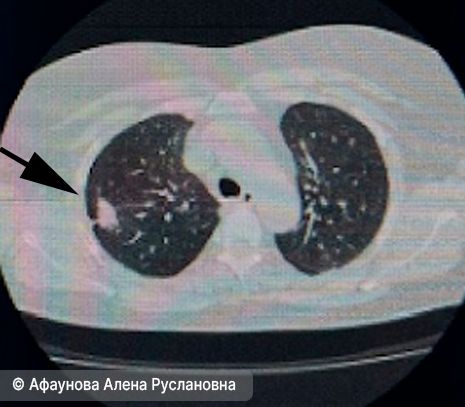

- Рентгенография органов грудной клетки. С помощью неё чаще всего выявляются уже запущенные стадии заболевания. Похожее исследование — компьютерная томография (КТ) органов грудной клетки с контрастным усилением (предпочтительно), т. е. с введением специальной жидкости в организм, чтобы уточнить состояние органов, сосудов и самой опухоли.

Периферический рак правого лёгкого